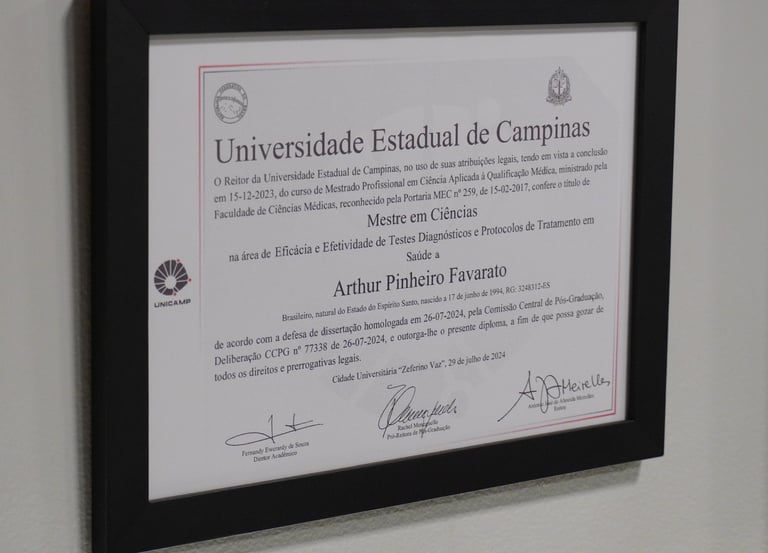

Mestrado em Ciências Médicas pela UNICAMP